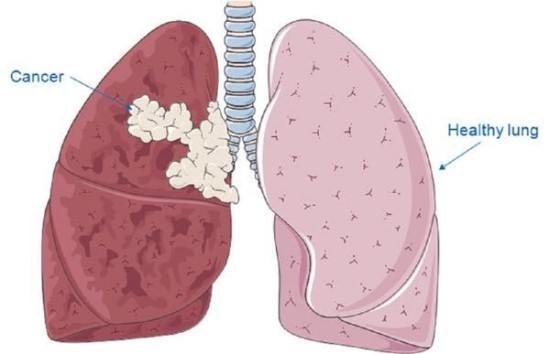

오늘은 단순한 감기와는 달리, 폐에 염증이 생기는 심각한 질환인 폐렴의 증상에 대해 이야기하려 합니다. 폐렴은 세균, 바이러스, 곰팡이 등 다양한 원인에 의해 발생하며, 특히 면역력이 약한 어린이나 노인에게 치명적일 수 있습니다.

폐렴은 보통 갑작스럽게 시작되며, 호흡기 증상과 함께 전신 증상이 복합적으로 나타납니다. 다음은 폐렴 환자들이 흔히 겪는 10가지 주요 증상입니다.

- 청색증

- 설명: 폐 기능이 심하게 저하되면 몸에 산소가 부족해져 입술이나 손톱이 파랗게 변하는 청색증이 나타날 수 있습니다. 이는 즉시 응급 처치가 필요한 매우 위험한 상태입니다.